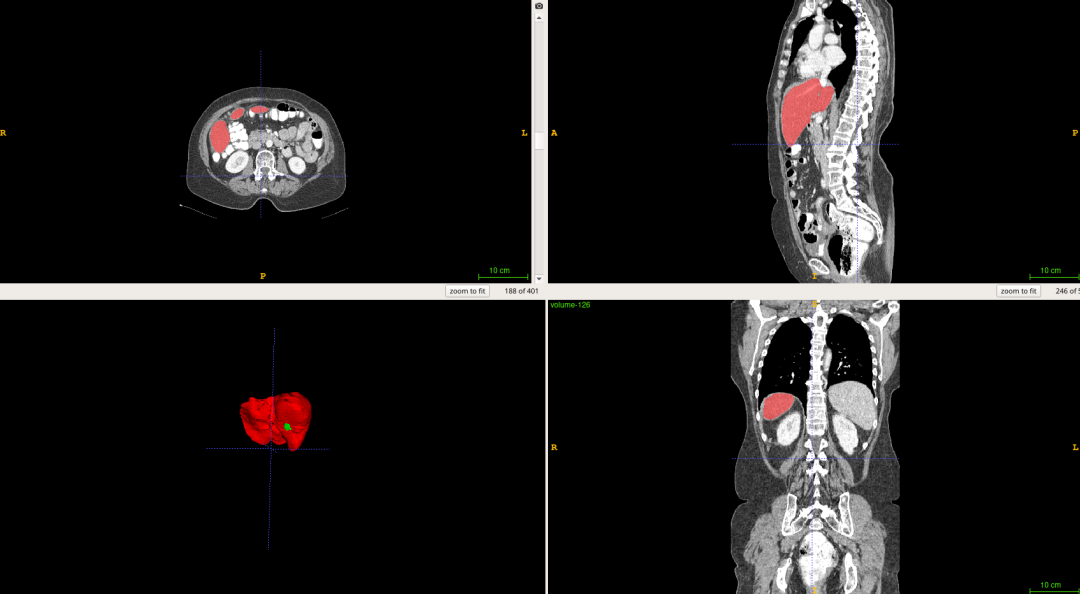

基于飞桨PaddlePaddle框架,我使用Res-Unet网络结构在 LiTS 数据集[2]上训练了一个分割网络,最终在肝脏和肝肿瘤上分别达到了 0.92 和 0.77 的分割准确率。LiTS数据集是目前最大的开源肝脏分割数据集,其中包含130名患者的CT扫描和医生对患者肝脏及肿瘤的分割标注,下图是数据集中的一个示例:

图1 肝脏分割示例